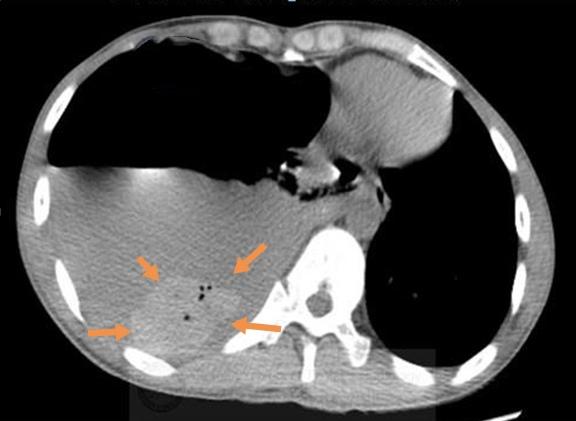

胸部CT显示右侧液气胸,胸腔积液和气体压迫肺组织,导致呼吸困难和不能深吸气,并且挤压心脏向左侧移位。

再看纵隔窗:

在大量灰色的胸水里,有一块椭圆形的小团块沉在水底,里面还有4个小气泡。

这个病人不是单纯的液气胸,准确点说,他是自发性血气胸,出血量在400ml以上了。